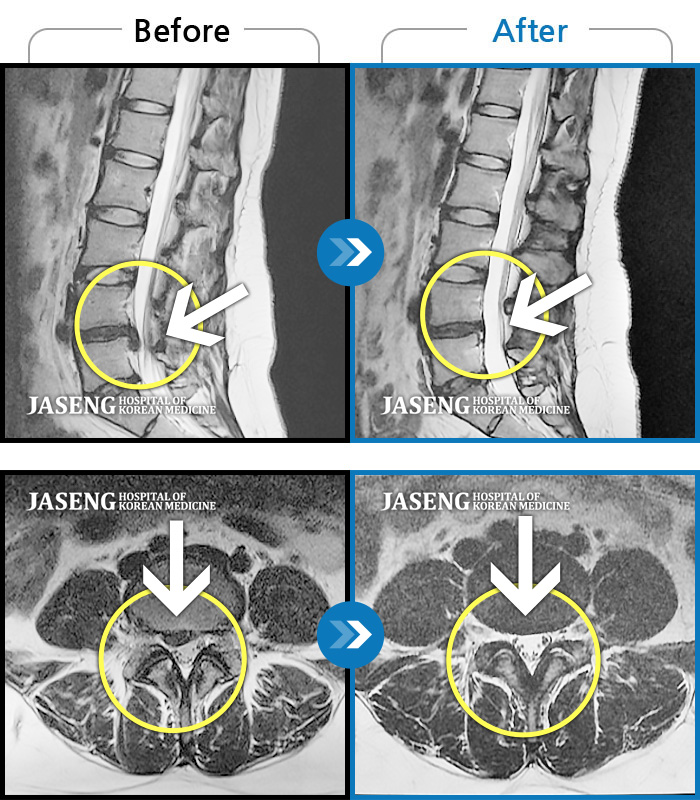

Before

After

환자에게 사전 동의를 받아 동일 조건에서 촬영되었습니다.

개인에 따라 치료 후 부작용이 발생할 수 있으니 의료진과 상담 후 치료를 진행하시기 바랍니다.

허리 및 우측 하지 통증

요통과 우측 하지부 당김 증상